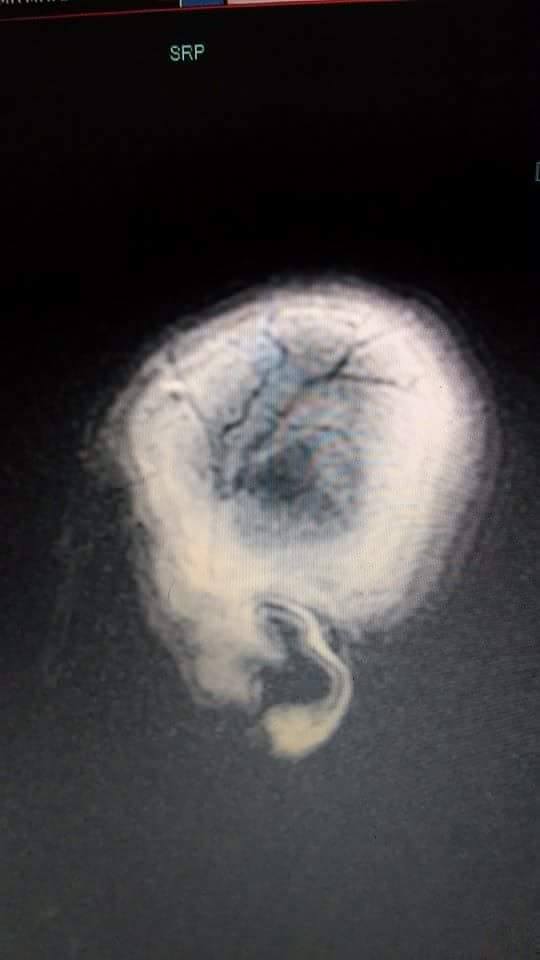

brain2 Share this: Share on Facebook (Opens in new window) Facebook Share on X (Opens in new window) X Share on Pinterest (Opens in new window) Pinterest Email a link to a friend (Opens in new window) Email Print (Opens in new window) Print More Share on Tumblr (Opens in new window) Tumblr Like Loading...